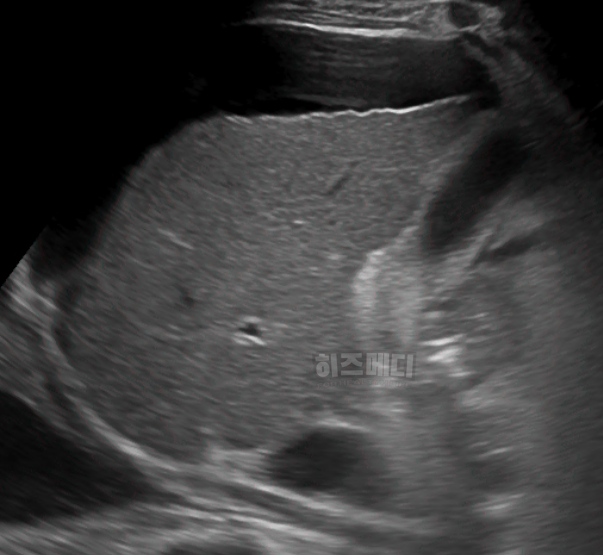

7) 간 초음파, CT, MRI

간 초음파, CT, MRI는 간의 구조적 문제나 질환을 더욱 정확히 확인할 수 있는 영상 검사입니다. 간의 크기, 형태, 결절 등을 확인하고, 간 질환이나 암의 유무를 확인하는 데 도움이 됩니다. 간 초음파는 비침습적이고 빠르게 진행할 수 있는 검사로, 주로 간염, 지방간, 간경변 등을 확인하는 데 사용됩니다.